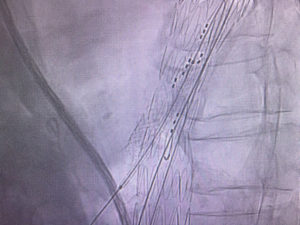

Gore Viabahn VBX balloon expandable covered stent might provide an excellent option for branched thoracoabdominal stent graft. Two VBX used today for successful bridging of coeliac axis and SMA branches. Easy delivery without sheath, great tractability, wide range of lengths and significant postdilatation bracket with no concerning shortening.